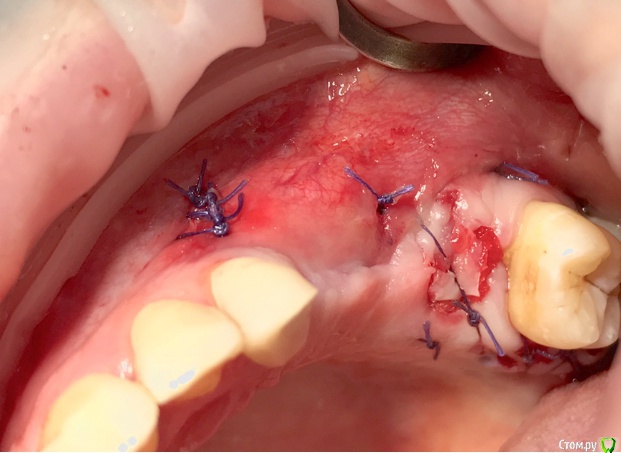

колесников Опубликовано 20 августа, 2019 Автор Поделиться Опубликовано 20 августа, 2019 Очередной случай тоннельной пластики альвеолярного гребня. Был небольшой бонус в виде лунки 26го зуба с дефектом вестибулярной стенки и оас. Лунка консервирована и закрыта «быстрым Ноймайером»,24,25 тоннельный графтинг. Графт тот же,шурос кортикальный без добавок.Контроль и имплантация через 4 мес,через неделю фиксация временной реставрации. Через 2-3 проверим на состоятельность. 4 Ссылка на комментарий